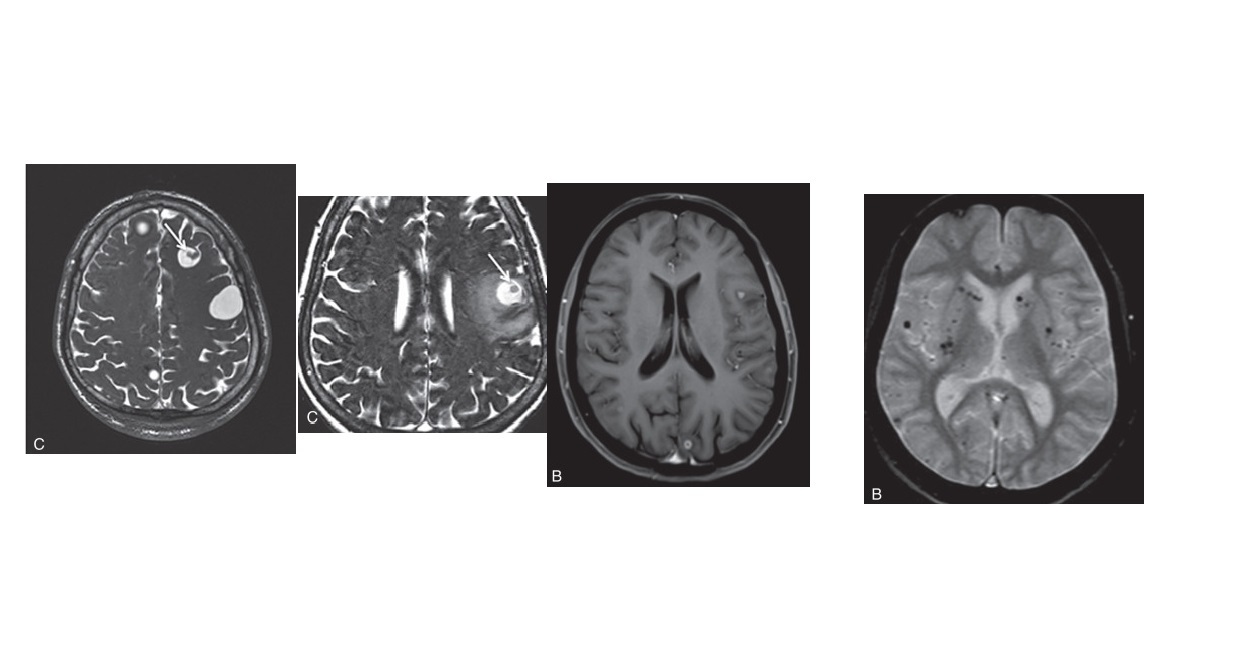

4 stages of Neurocysticercosis (VCGN) ?

Vesicular -

Thin walled cyst - CSF pattern. No pericystic oedema. (Low T1/T2)

scolex (hole with dot appearance)

Colloidal -

Hyperdense cyst - proteinaceous fluid) (High T1/T2) . **pericystic oedema and enhancement **

scolex (hole with dot appearance) can persist

Granular -

Cyst shrinks, small ring-enhancing or solid nodule enhancement. less pericysitc oedema

Nodular -

Small calcified lesion. no oedema or enhancement. hypointense on all sequences due to calcification